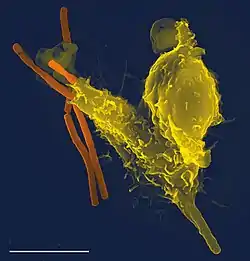

- Microbiology